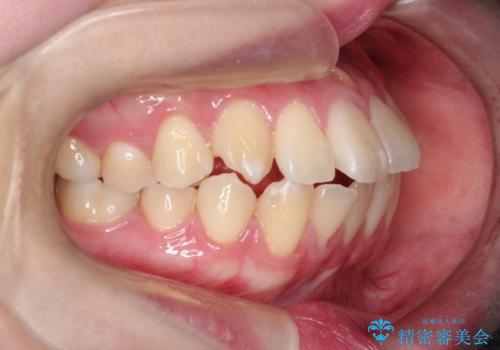

【インビザライン】歯を抜かずにできるだけ前歯を下げたい

- 前歯の前突を主訴に来院されました。

インビザライン を用いて、歯並びの改善を行うことができました。